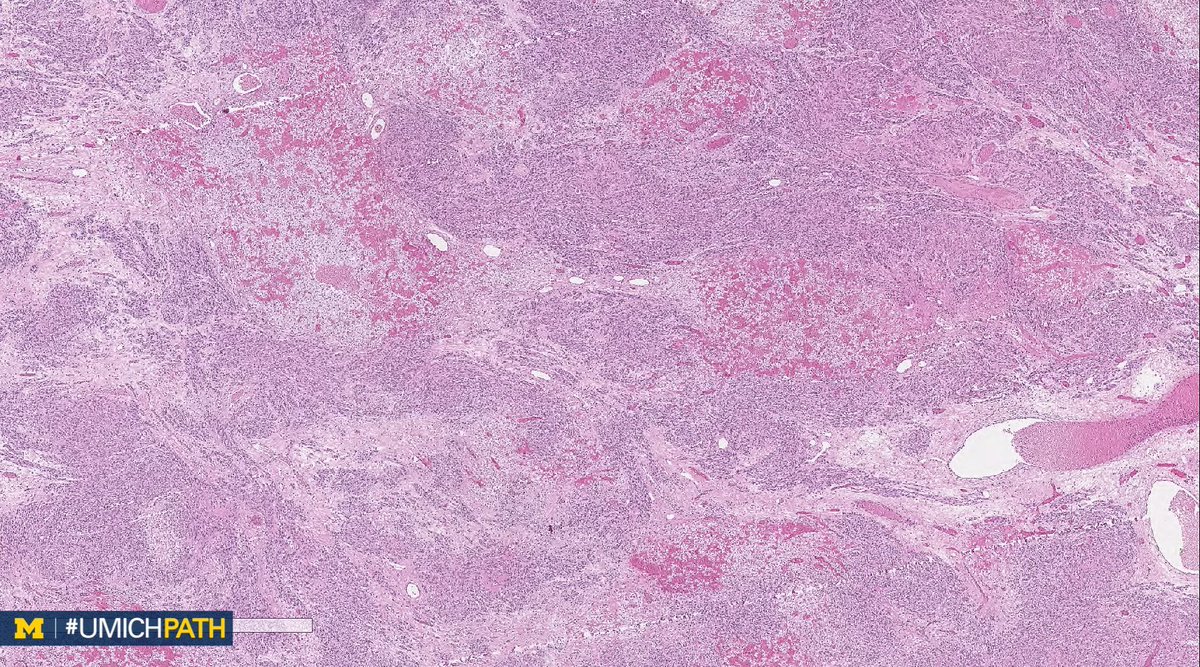

We're sharing 2 cases today since we missed #GYNPath Day 5 last week. What’s your #DailyDx of this uterine mass? We’ll tweet the answer and some quick facts tomorrow! #UMichPath

What’s your #DailyDx of this uterine mass?

We’ll tweet the answer and some quick facts tomorrow! #UMichPath

A: Lipoleiomyoma. A variant of uterine leiomyomata. Gross: Well circumscribed mass with alternating yellow and white areas. Histo: Variable admixture of bland smooth muscle cells and adipocytes. Very rarely can have glandular elements (adenolipoleiomyoma). #GYNPath #DailyDx